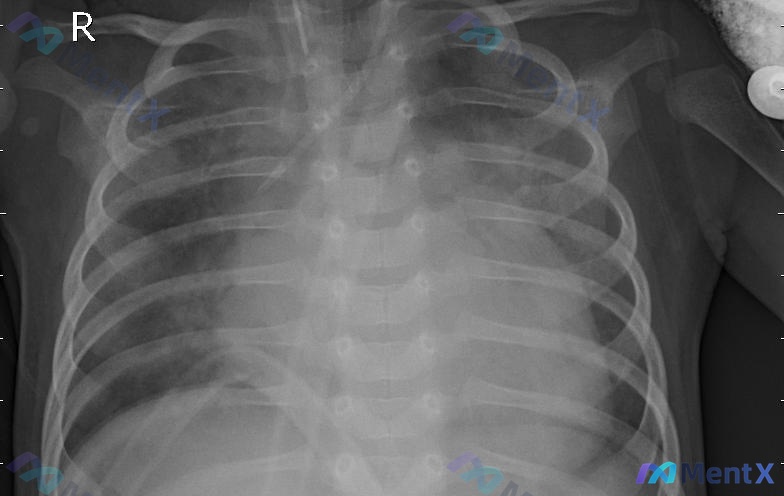

整理了一份带影像分析的床旁胸片资料,觉得很适合讨论危重症影像的鉴别思路。 先不剧透分析里的倾向性,先看核心影像表现: - 患者是气管插管状态,导管位置尚可 - 双肺野(尤其中下肺)透亮度普遍减低,弥漫磨玻璃/斑片状渗出,左肺中下野更显著 - 心影增大(但投照是床旁AP位,且吸气不足) - 双侧肋膈角...